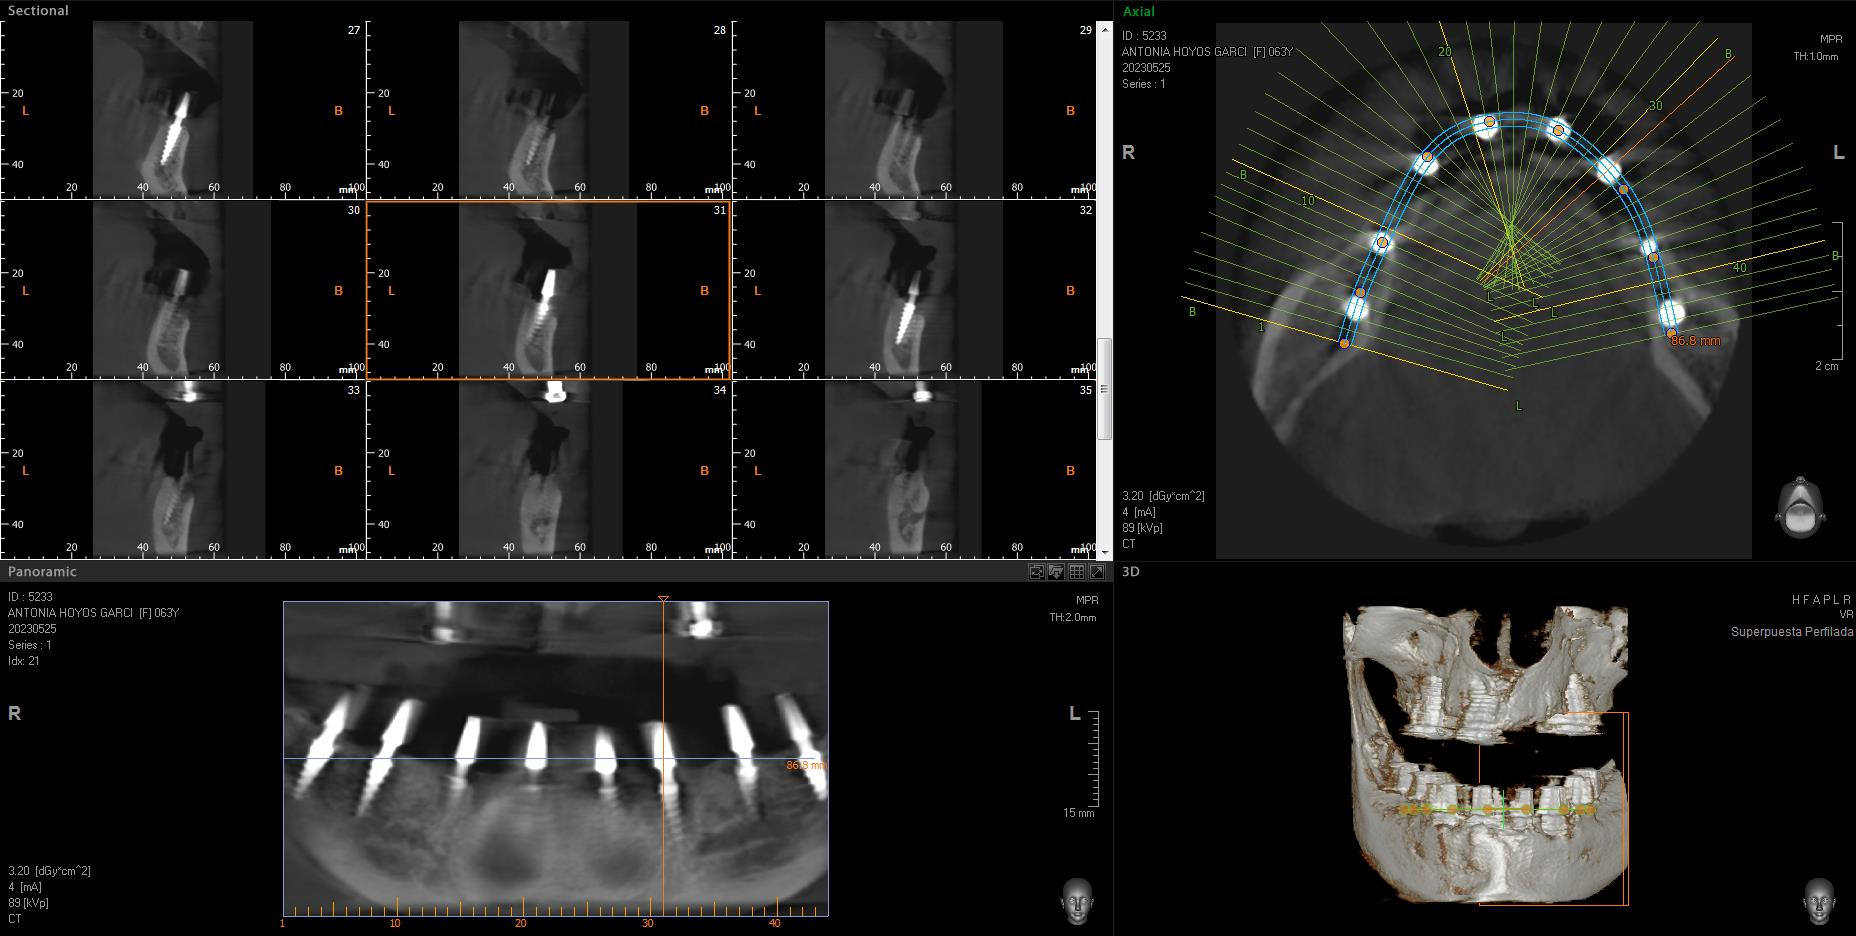

Implantes SLD-c

Secuencia de imágenes RX, antes y después de la inserción de implantes SLD-c en la parte inferior de la boca.

Paciente mujer de 65 años.

- Radiografía previa a la operación.

- Colocación implantes Radhex SLD-c parte inferior.

- Colocación implantes Radhex SLD-c parte inferior con soldadura.